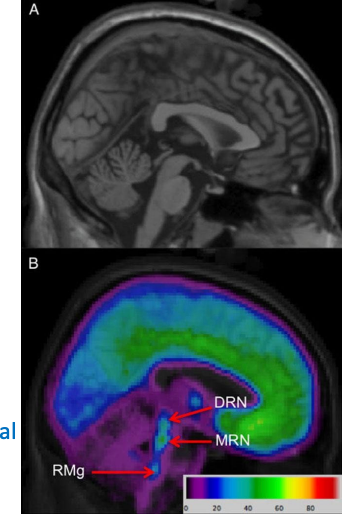

Raphe is site of 2 major nuclei.

MRN → limbic/prefrontal cortex → mediates fear/anxiety.

DRN → Prefrontal cortex, basal ganglia, PAG → Modulates cognitive/behavioural components.